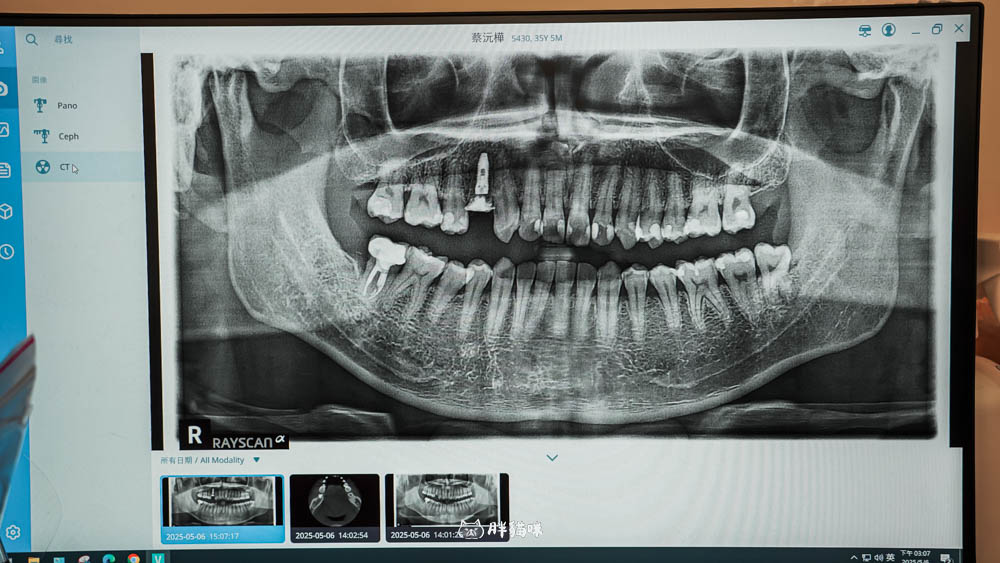

我們首先在櫃檯報到,填寫好一些基本資料,接著最重要的就是進行3D 斷層掃描。

這步驟超關鍵!不像傳統 X 光,這個 3D 斷層 Ray 可以清楚看到神經走向,如果需要處理頂鼻竇的話,還能看到鼻竇的位置,可以輔助醫生精準評估治療方向。